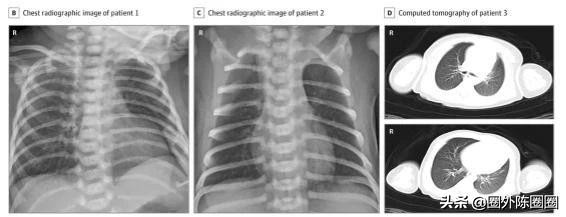

近日于《JAMA》发布的一项对中国武汉儿童医院33名确诊COVID-19孕妇所生婴儿的跟踪研究中,研究人员发现,经鼻咽拭子和肛拭子新冠病毒核酸检测,其中有3例(9%)出现早发型感染。

新生儿影像学表现

这3名受感染的婴儿都通过剖腹产出生,出生时即与母亲分离,分娩过程中也实施了严格的感染控制和预防程序,且羊水、脐带血和母乳的病毒检测结果均为阴性,尚不清楚他们是如何感染病毒的。